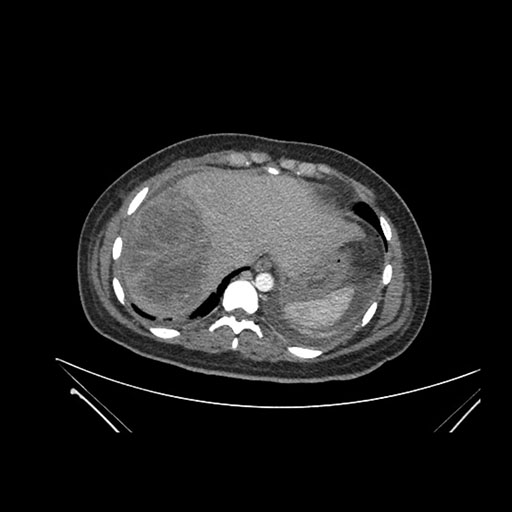

Imaging Analysis

Look through the patient's CT scan to identify any areas of concern for the necessary procedure.

Axial Venous

Based on initial findings, which issue(s) would you be most concerned about?